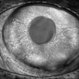

- Diabetic Rubeotic Glaucoma

- rubeosis, diabetic rubeotic glaucoma

- DR Rubeosis.